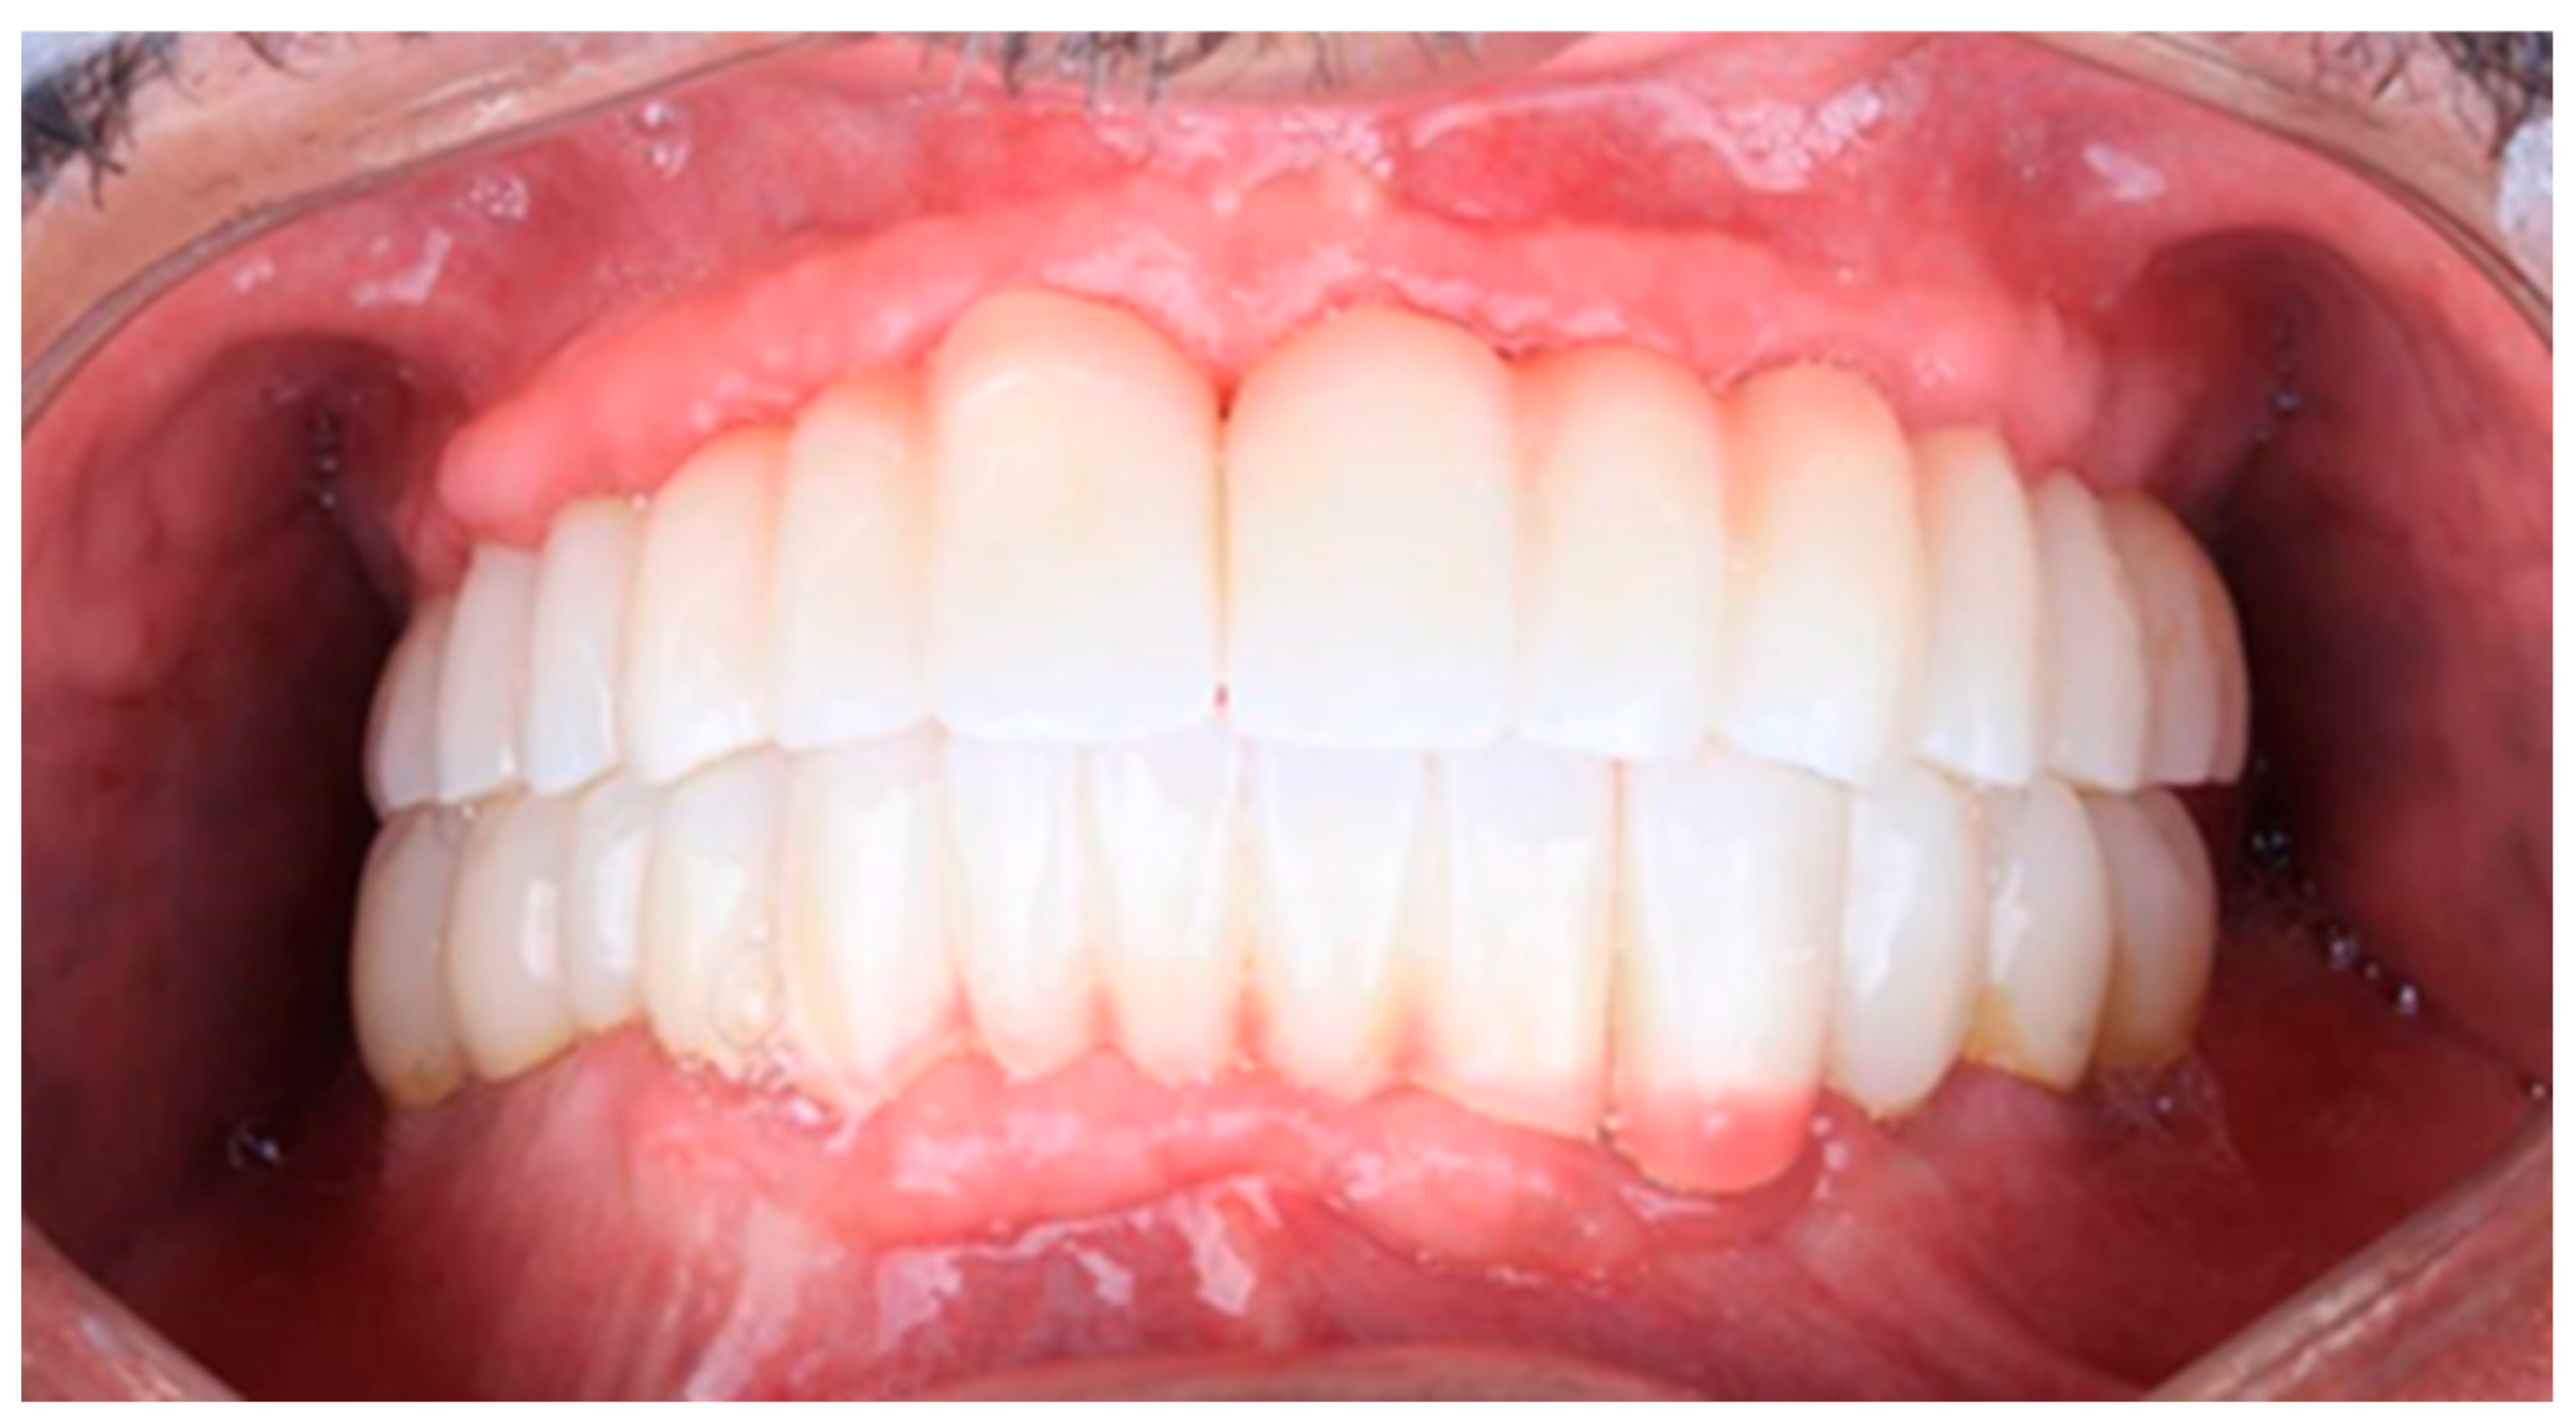

Figure 16. Follow-up photo.

2.6. Sixth Visit

During the three-year follow-up period from October 2022 through September 2025, the patient was regularly recalled for evaluation. The peri-implant soft tissues remained healthy throughout the observation period. The gingiva surrounding the implants was consistently pink, firm, and showed no bleeding or suppuration upon probing of the peri-implant sulcus. At the last visit, probing depths ranged from 2–4 mm (mean 3 mm) in the maxillary arch and 1–3 mm (mean 2 mm) in the mandibular arch. No clinical signs of inflammation, edema, or granulation tissue were observed, indicating stable peri-implant mucosa and sustained biocompatibility of the materials used. Radiographic assessment revealed no crestal bone loss, and the prosthetic components remained functionally and esthetically intact, with no evidence of wear, fracture, or loosening. The patient reported high satisfaction regarding comfort, function, and appearance, further supporting the clinical success and reliability of this treatment approach (Figure 16 and Figure 17).